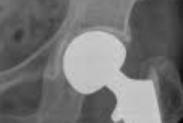

髋臼骨折

628健康网为您分享有关髋臼骨折的症状,髋臼骨折的治疗方法,髋臼骨折的预防知识,髋臼骨折的症状图片,髋臼骨折吃什么药,髋...